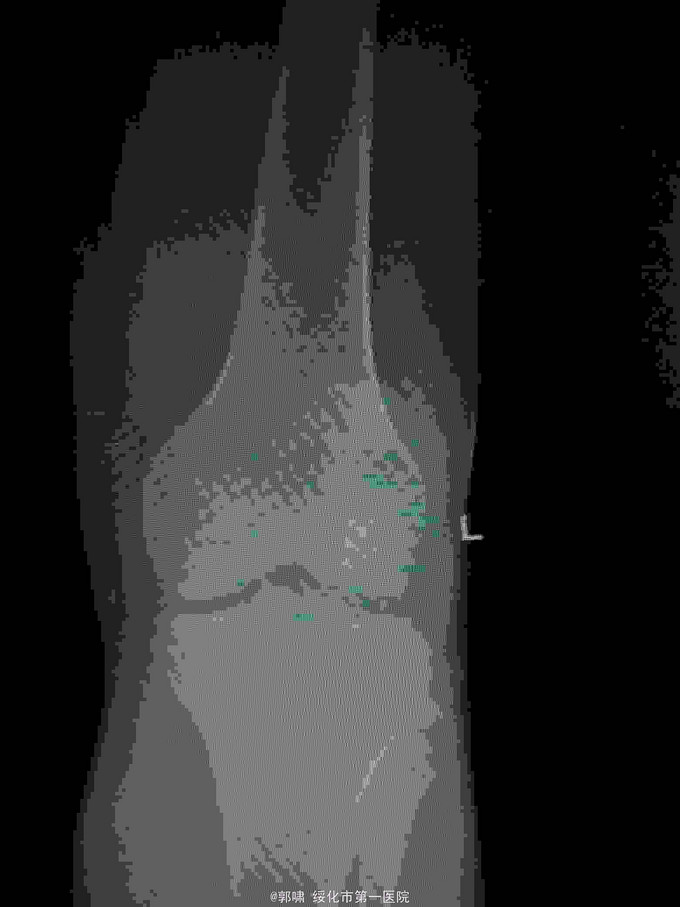

左膝关节摔伤,肿胀,畸形,活动受限一小时。收入院。患者于一小时前滑倒摔伤。当即倒地,左膝关节肿胀,畸形不能行走。门诊拍片示:左膝关节髌骨骨折,断端移位。门诊以左髌骨骨折收入院。

左膝关节肿胀,局部畸形,不能下地行走。浮髌试验阳性。拍片示:左髌骨骨折。

诊断:左髌骨骨折。立即予以腰麻下行切开复位内固定术。术中复位骨折,缝合筋膜,冰水浸泡髌骨爪约10分钟。待髌骨爪变软。选取合适大小的髌骨爪。应用记忆合金髌骨爪内固定。立即用40°温盐水热敷局部。使记忆合金加速抓紧。环抱。缝合爪齿二道,防止脱落。缝合关节囊,韧带组织。术毕。